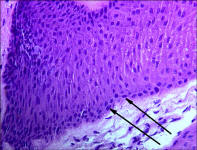

A New 464 Page Textbook, in Full-Color with 630 Pictures and Drawings, by Pete Ramey

A Few Pictures from the book:

Photos referenced in text from Bidwell/Bowker, Bowker, Clayton, Cowles, Hampson, Kellon, Ramey, Ridgway, Sullivan, Taylor, Watts.